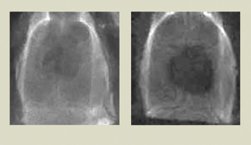

BUILDING BONES. A rat’s skull regenerates better with a new bone-promoting scaffold (left) than with a less-sophisticated scaffold (right).